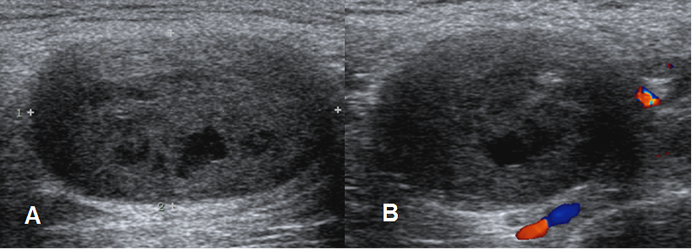

Mediante ecografía es difícil diferenciar un neurofibroma, de un schwanomas. Se encuentran como lesión hipoecoica, bien definida y fusiforme, que sigue la distribución de una raíz nerviosa. (9). (Fig 173 B).

Fig 173 B. Neurofibroma.

A y B: Ecografía. Imagen ovalada, de bordes bien definidos y consistencia heterogénea, con algunas zonas quísticas. En el doppler es poco vascularizada y corresponde a neurofibroma.